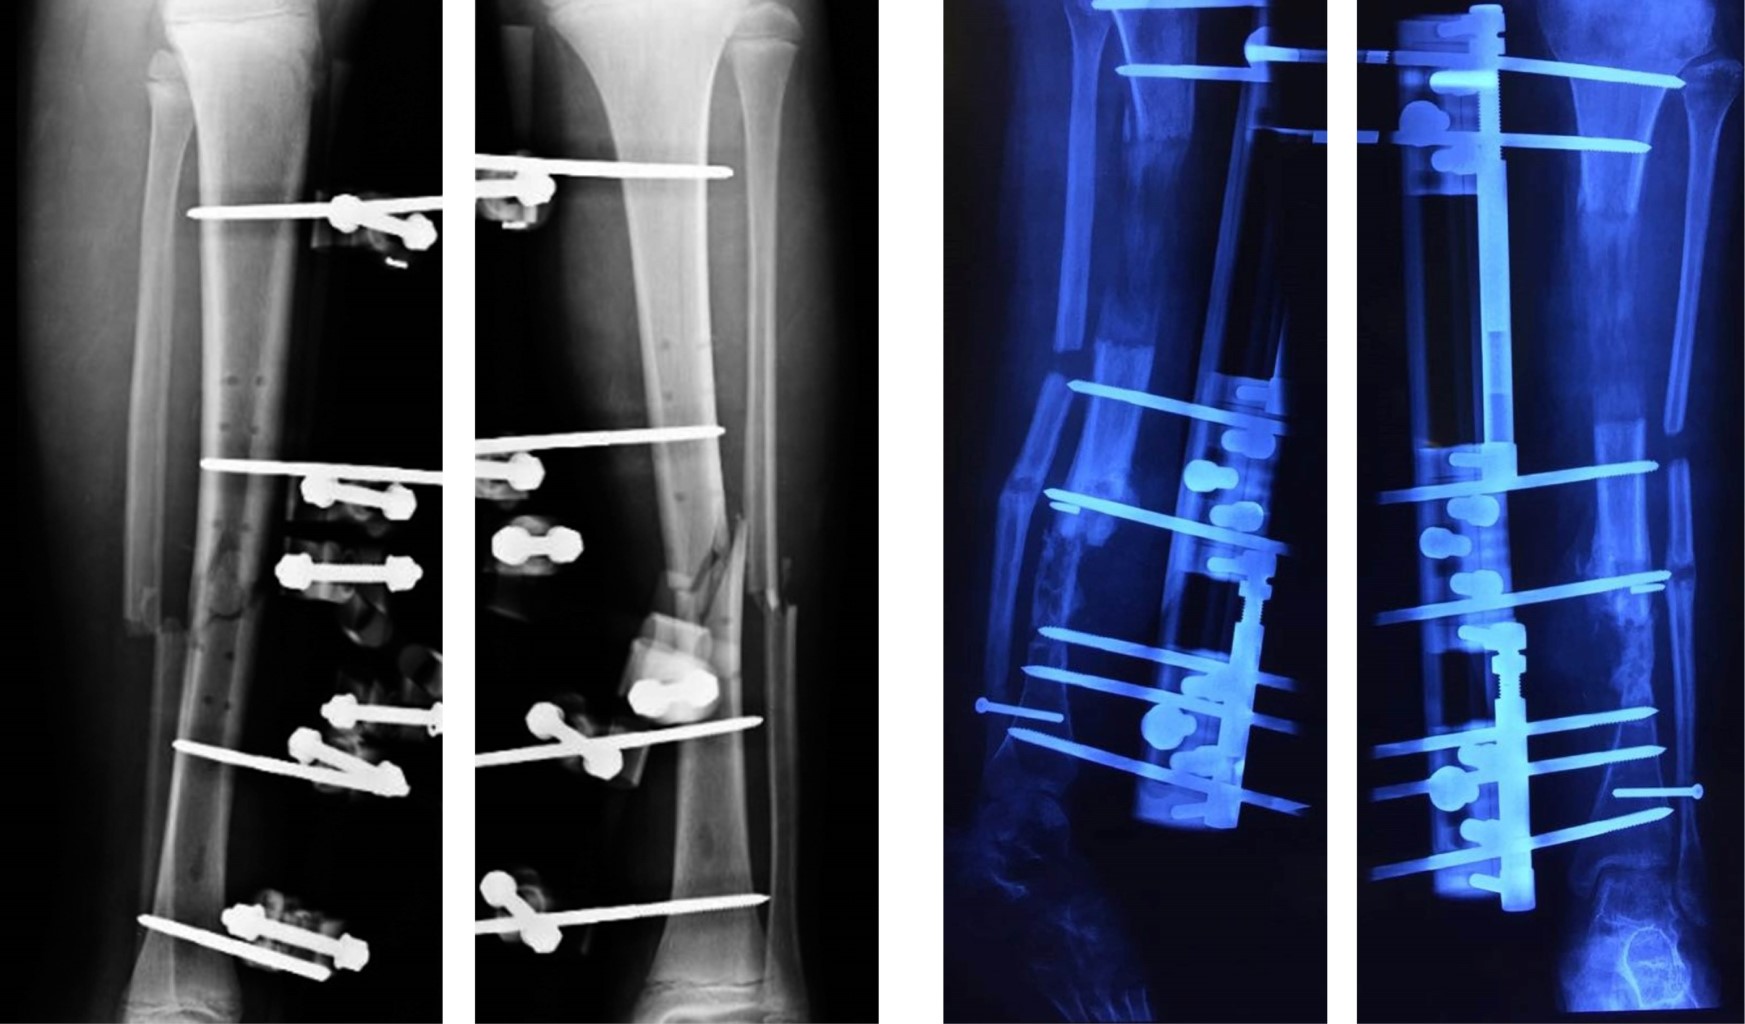

Se realizó un estudio retrospectivo, analítico y descriptivo de pacientes con pérdida ósea de miembros inferiores con pseudoartrosis infectada, que fueron tratados mediante transportación ósea con la técnica de De Bastiani (Tabla 1), con el sistema de fijador externo tipo monorriel. Se incluyeron en el estudio aquellos pacientes con pseudoartrosis infectada, de uno u otro sexo, con una pérdida ósea de tibia de más de 5 cm, manejados en el servicio del Centenario Hospital "Miguel Hidalgo" (Figura 1). Se excluyeron los pacientes que no presentaron infección de pseudoartrosis. Se realizó una planeación quirúrgica para todos los casos mediante un protocolo preoperatorio general que incluyó estudios de laboratorio preoperatorios completos con reactantes de fase aguda, y se solicitaron controles de radiografías en la consulta externa. Sólo una paciente no comenzó el tratamiento inicial en este hospital, por lo que no contamos con las radiografías iniciales (Figura 2). Los resultados después de la corticalización del segmento transportado fueron evaluados desde el punto de vista óseo y funcional, utilizando el sistema descrito por Paley y colaboradores. Para los resultados óseos se valoraron cuatro criterios: consolidación, infección, deformidad y discrepancia de extremidades.9 Los resultados funcionales se basaron en cinco criterios: cojera significativa, deformidad rígida en equino del tobillo, distrofia de tejidos blandos (manifestada por hipersensibilidad dérmica o insensibilidad), dolor e inactividad (que el paciente quedara inhabilitado para las actividades diarias). De acuerdo con este sistema, un excelente resultado funcional es el que logra actividad sin ninguno de los otros criterios; un resultado bueno es el que realiza actividad pero con uno o dos de los otros cuatro criterios; regular es cuando logra actividad pero presenta tres o cuatro de los otros criterios o ameritó amputación; y malo en aquel que no logra actividad individual a pesar de los otros criterios.5

El método de De Bastiani consiste en la estabilización de los fragmentos comprometidos con tornillos troncocónicos no transfictivos, los cuales se fijan a un riel rígido con tres cabezales deslizantes (sistema de fijación externa tipo monorriel).2 Con el paciente en decúbito dorsal bajo bloqueo subaracnoideo en mesa radiolúcida y con intensificador de imágenes, se determinan líneas paralelas a la superficie articular, se colocan tres cabezales provisionales en regleta de elongador, se coloca un primer tornillo en cabezal proximal paralelo a articulación de rodilla, el segundo tornillo en cabezal distal paralelo a articulación de tobillo y un tercer tornillo en cabezal intermedio paralelo a la diáfisis de la tibia, después se colocan los tornillos restantes, quedando tres tornillos por cabezal, se cambian cabezales provisionales por los definitivos (Figura 3). Después se realiza incisión de 1 a 1.5 cm en la región proximal o distal según el sitio seleccionado para la corticotomía hasta periostio, se incide éste de manera longitudinal y se procede a perforar agujeros en las caras anteromedial y anterolateral del hueso para perforar la cortical posterior con broca 3.2 mm, mismos que se realizan con la menor distancia entre sí. A continuación, los agujeros se unen con un osteótomo una vez completada la osteotomía, porque la parte posterior se rompe de manera espontánea debido a la tensión aplicada antes del montaje. Se separan los segmentos mediante el distractor para asegurar que la osteotomía es completa y se confirma con el intensificador de imágenes. Se vuelven a aproximar los segmentos a distraer, sometiéndolos a una compresión leve y se aprietan las tuercas de bloqueo. Se cierra el periostio y la herida sin dejar drenajes. Se entrena al paciente y familiares sobre cómo realizar la distracción, cuándo iniciarla, frecuencia y sentido de la vuelta de la unidad de compresión-distracción, se le recomienda al paciente anotar en un cuaderno hora y fecha de distracción y sus observaciones como sensación de tracción, dolor o cualquier eventualidad. De no existir contraindicación alguna, se egresa al segundo día del postoperatorio. La fase de reposo dura en promedio 10 días. La distracción se realiza a razón de 1 mm por día, girando cuatro veces al día un cuarto de vuelta en sentido antihorario la unidad de compresión-distracción (0.25 mm cada 6 horas). Este promedio de distracción se acelera temporalmente cuando se observa una osificación rápida, o se reduce si la osificación es lenta o el paciente padece dolor o contractura muscular. La distracción es vigilada mediante controles radiográficos. Se cita a los 10 días del postoperatorio para valorar las heridas, retirar los puntos y verificar que entendió cómo iniciar la distracción. Tres citas semanales al inicio y quincenales posteriormente con radiografías de control. La fase de reposo dura en promedio un día. La distracción se realiza a razón de 1 mm por día, girando cuatro veces al día un cuarto de vuelta en sentido antihorario la unidad de compresión-distracción (0.25 mm cada 6 horas). Este promedio de distracción se acelera temporalmente cuando se observa una osificación rápida, o se reduce si la osificación es lenta o el paciente padece dolor o contractura muscular. La distracción es vigilada mediante controles radiográficos. Se cita a los 10 días del postoperatorio para valorar las heridas, retirar los puntos y verificar que entendió cómo iniciar la distracción. Nueva cita a los 10 días con radiografía de control para valorar que la distracción se realiza de manera correcta. Se le recomienda la carga parcial de aproximadamente 15 kg. Después se cita cada 30-40 días con radiografías de control para comprobar que se produzca la osteogénesis, en cuyo caso se continúa la transportación. Si la densidad del neoformado es pobre pero uniforme, se suspende la distracción por una o dos semanas. Si el neoformado es irregular, se comprime el segmento uno o dos centímetros a la misma velocidad de la distracción hasta que el callo sea uniforme, a continuación se reinicia la transportación. Al final de la transportación, cuando hay contacto de los dos fragmentos, la radiografía debe mostrar un callo uniforme (Figura 4). Se bloquea el cabezal del alargador para mantener el hueso nuevo en neutralización estable, el compresor-distractor es entonces retirado. Cuando así se requiere, una nueva cirugía puede realizarse para reavivar los bordes de la zona de contacto y colocar injerto para acortar el tiempo de consolidación, el soporte de carga en esta fase de neutralización se incrementa gradualmente en función del grado de mineralización del neoformado. Cuando la radiografía demuestra que el segmento es uniformemente denso y opaco, se dinamiza el elongador aflojando la tuerca del cabezal proximal y se bloquean las del cabezal medio y distal. Una vez que se ha logrado la corticalización completa, se procede al retiro del elongador y los tornillos troncocónicos, se realiza en quirófano y bajo anestesia general endovenosa (Figura 5).

Figura 1